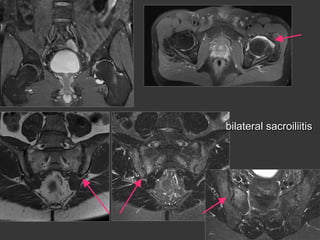

Sacroiliac Joint

–structural Lesions in MR

erosions

T1

Fatty areas

sclerosis

ankylosis